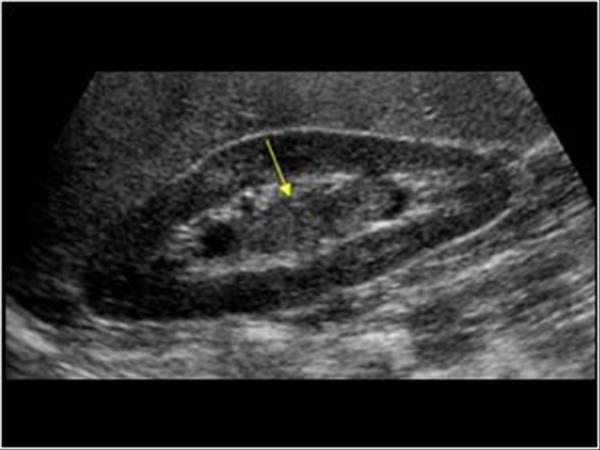

Hypertrophic Pyoric Stenosis

Fever